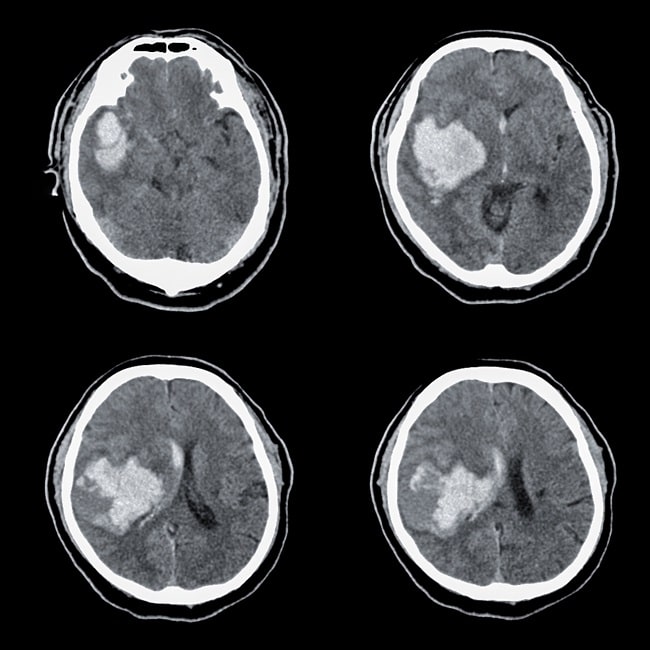

Terdapat perubahan protokol studi juga untuk mengubah agar interval waktu dari onset gejala perdarahan ke pencitraan baseline ≤6 jam (sebelumnya ≤12 jam). Hematoma harus terlihat pada CT scan otak atau MRI otak dalam 2 jam sebelum randomisasi. Pasien dieksklusi jika memiliki Glasgow Coma Scale (GCS) <7 saat pengambilan consent atau memiliki skor NIHSS >35 atau jika memiliki riwayat kejadian trombotik dalam 2 minggu sebelum diikutkan dalam studi.

Volume hematoma diestimasi dengan CT atau MRI oleh investigator di lokasi (sesuai protokol lokal) dan dinilai kembali di suatu pusat dengan program semiotomatis oleh dokter terlatih yang tidak mengetahui pembagian grup pasien (blinded). Metode ini digunakan untuk semua pasien kecuali 7 orang. Hasil pencitraan dibaca di laboratorium tetapi juga dinilai kembali di pusat oleh komite yang tidak mengetahui (blinded) tentang penilaian final.